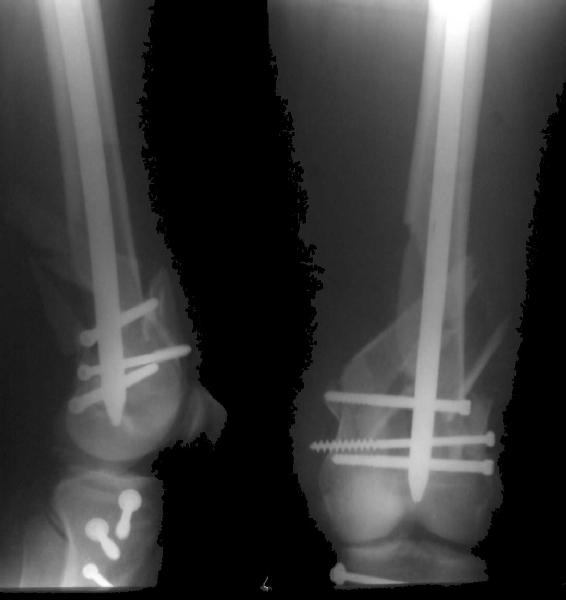

And why LISS is superior here than nail?

Look what we would have done.